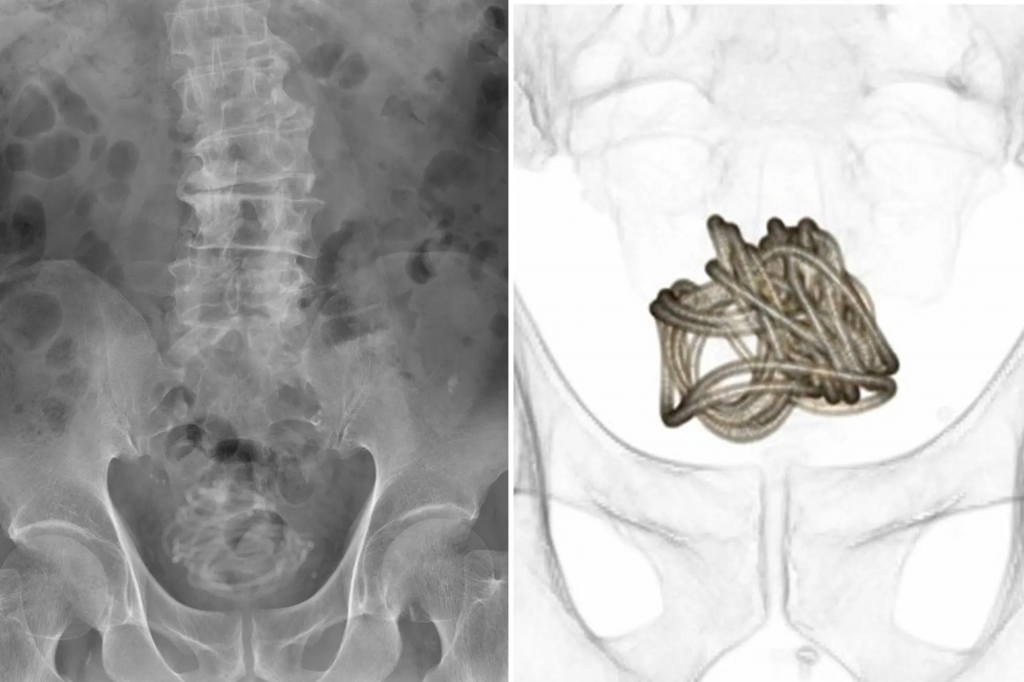

Medical images showed the jump rope without the handles tangled and stuck inside the man’s bladder. While the reason for this act is not known, the rope has been removed surgically without any complications.

X-ray was conducted, and it showed a wire-like coiled body in his bladder. Since it was impossible to remove it the same it got in, surgery had to be performed on the patient to get it out. Thankfully, there were no complications and he made a full recovery without long-term injury.